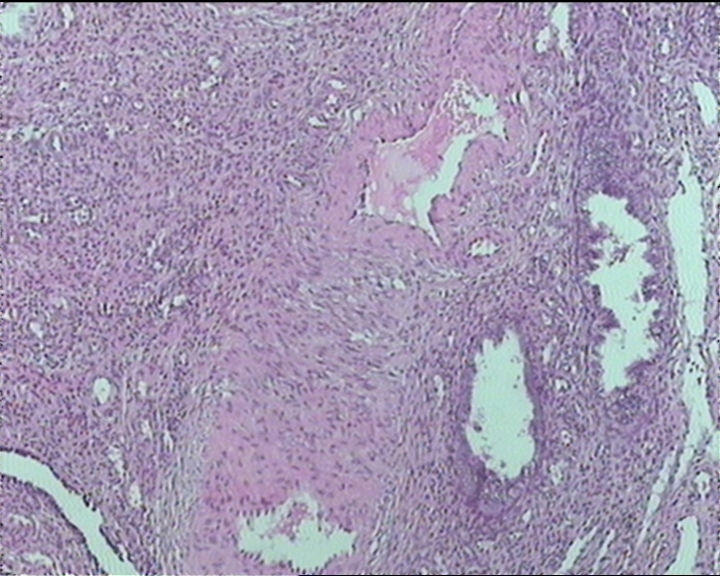

54岁女性,临床“宫颈息肉”送检;巨检:组织一块1。5*1CM,灰红。

输卵管粘膜化生

细胞及腺体均有异形,图6、11、16象有纤维间质反应,考虑高级别上皮内瘤变/原位癌,腺癌不能除外。

Sternberg病理学上诊断宫颈原位腺癌的标准是腺体的上皮去粘液分化,呈乳头状或筛网状增生,核分裂易见,这例显然达不到此标准。此例还是归入到腺上皮不典型增生为好。

It is benign. Benign endocervical polyp with tubal metaplasia.

杨老师说它是良性的,是个颈管内膜息肉伴输卵管上皮化生,良性